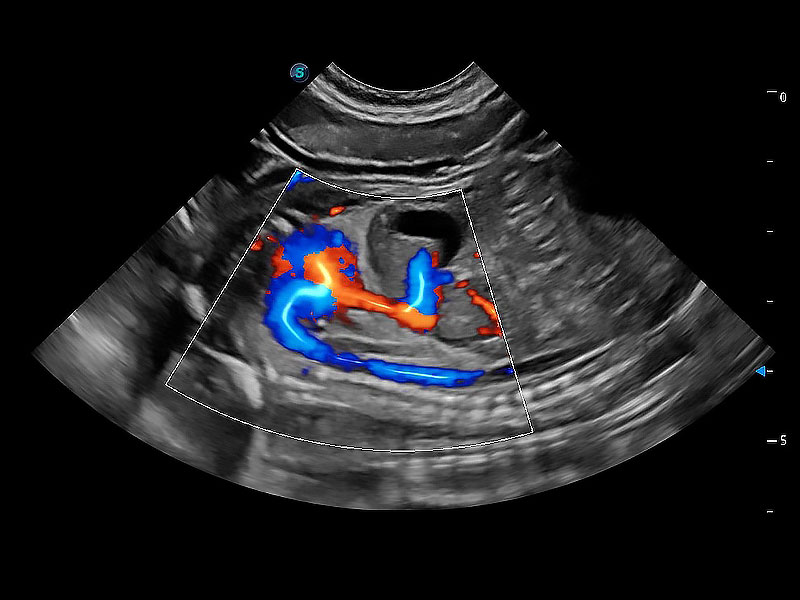

(犬)胎儿四腔心

(犬)胎儿主动脉弓立体血流